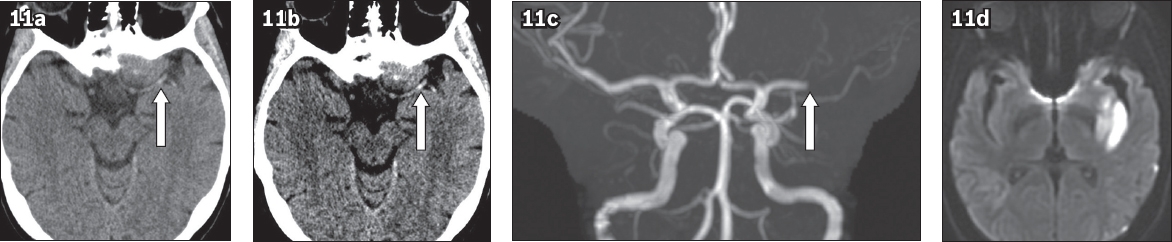

Fig. 11

(a) Non-contrast CT image of the brain obtained in standard window setting shows a probable focal hyperdensity in the M1 segment of the left middle cerebral artery (MCA; arrow) in a patient who presented with acute left hemispheric stroke. (b) Non-contrast CT image adjusted to stroke window settings shows a more conspicuous left hyperdense MCA sign (arrow). This emphasises the importance of interpreting non-contrast CT of the brain using two different window settings. (c) Time-of-flight MR angiogram shows complete occlusion at the M1 segment of the left MCA (arrow). (d) Diffusion-weighted MR image of the brain shows restricted diffusion in the left MCA territory, confirming the diagnosis of acute infarct.